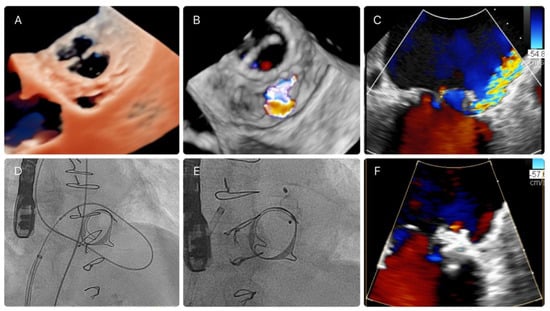

2.3. PVL Closure Technique and Characteristics of the Procedure

2.4. Imaging Data